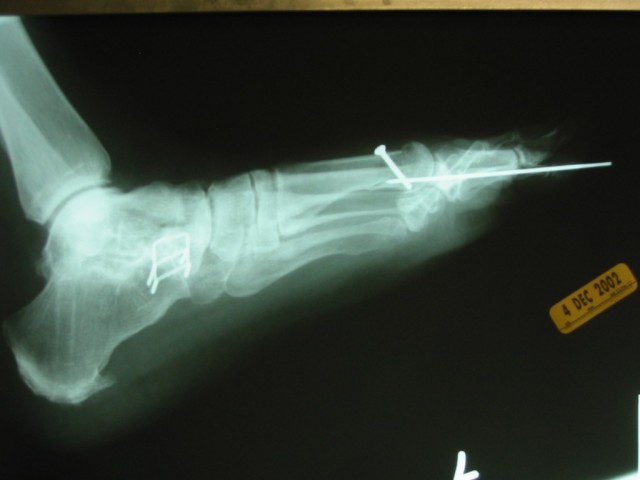

In Betty Lou's case, it included cutting and realigning the bone, holding it in place with a screw until it healed, and adjusting the tightness of a tendon and a joint capsule. Since the second toe had also been affected, it also was realigned and held in place by a really long pin. You can tell by the staples that this is the same foot that had the previous operation.